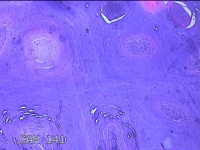

右侧拇指掌侧结节

性别

女

年龄

25岁

临床诊断

皮下结节

一般病史

发现右侧拇指结节2个月余。

标本名称

大体所见

灰白粉红色带皮肤样结节1.5x0.5x0.3cm一个,表面糜烂,切开结节呈实性,切面灰白粉红色,质软。